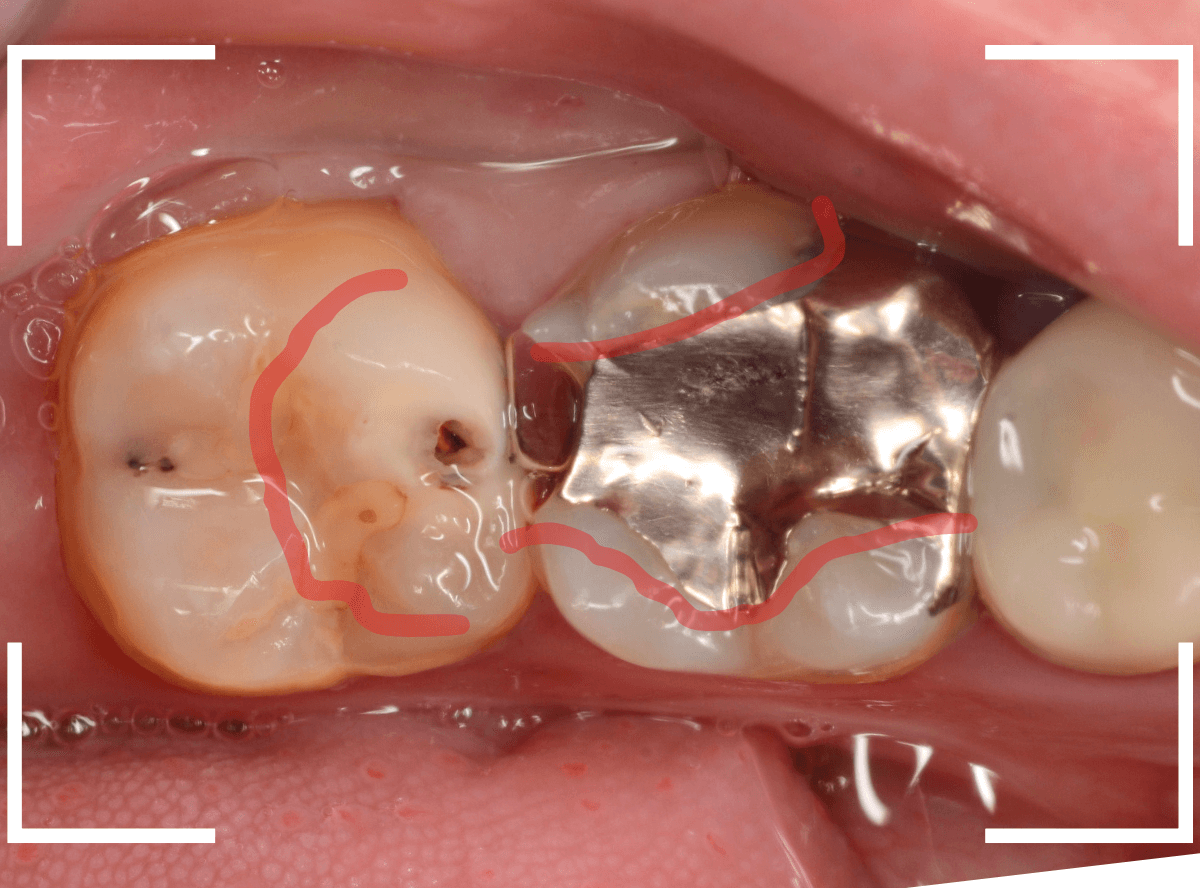

金属を外して、ある程度虫歯を除去したところです。

金属の下にしいてあるセメントも劣化してますので、中が虫歯になっていないかどうか、セメントも除去して調べます。

セメントまで除去したところです。

神経まで近い、かなり深い虫歯になっているのがわかります。

ここからは別の器具も併用して、虫歯を除去します。